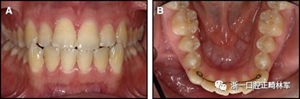

圖3.極軟弓絲完全完好,在多個(gè)空間平面上的拱形歪斜,右側(cè)尖牙的面部傾斜以及右側(cè)側(cè)切牙和中切牙在相反方向上的扭矩:A,頰面視圖; B,咬合面視圖。